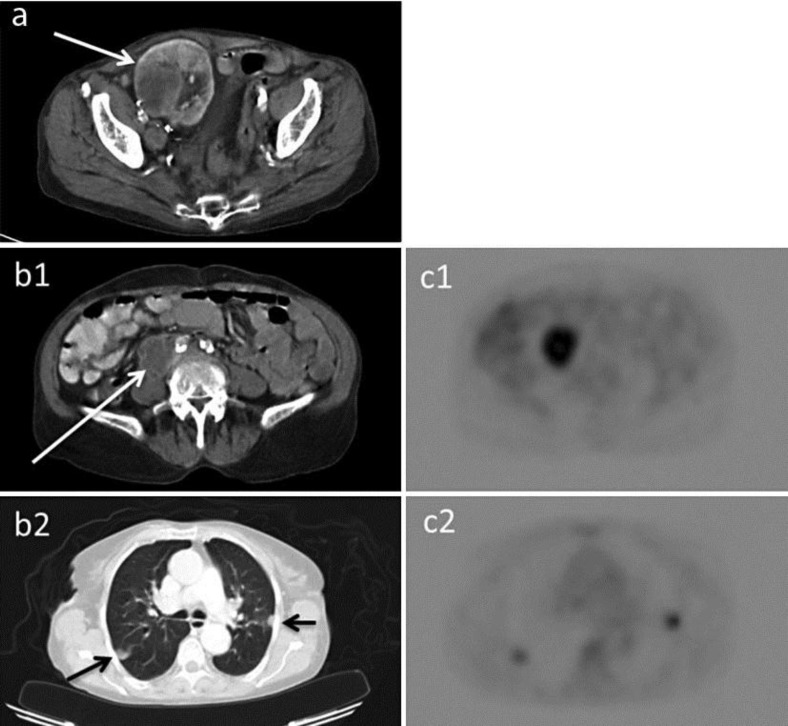

已知BK病毒(BKV)可引起儿童亚临床感染。病毒潜伏在人体内,主要存在于尿路上皮中。在开始免疫抑制治疗后,肾移植受者可发生再激活。BKV可引起出血性膀胱炎、输尿管狭窄和免疫功能低下患者的BKV肾病。此外,一些病例报告表明BKV感染与尿路癌的发展之间存在关联。到目前为止,已经在体外和动物模型中观察到BKV的致癌潜力;然而,其在人类中的致癌能力尚不清楚。我们报告一个59岁的病人谁发展为低分化肾细胞癌在她的肾移植,肺和腹部转移。手术切除同种异体移植物和停止免疫抑制治疗导致转移性疾病的完全解决。

BK virus (BKV) is known to cause subclinical infection in childhood. The virus remains latent in the human body, mainly in the urinary tract epithelium. After initiation of an immunosuppressive treatment, reactivation can occur in renal transplant recipients. BKV can cause hemorrhagic cystitis, ureteral stenosis and BKV nephropathy in immunocompromised patients. Furthermore, a number of case reports suggest an association between BKV infection and the development of urinary tract cancer. So far, an oncogenic potential of BKV has been observed in vitro and in animal models; however, its oncogenic capacity in humans remains unclear. We report the case of a 59-year-old patient who developed a poorly differentiated renal cell carcinoma in her renal allograft, with pulmonary and abdominal metastasis. Surgical removal of the allograft and cessation of the immunosuppressive therapy resulted in complete resolution of the metastatic disease.